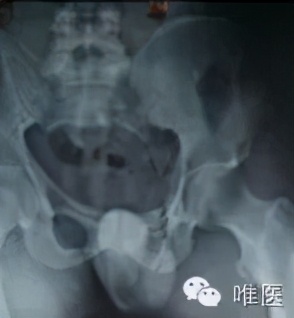

患者男性,26岁,高处坠落伤,腰骶部被厚重的铁门砸伤。

▼ 术前照片